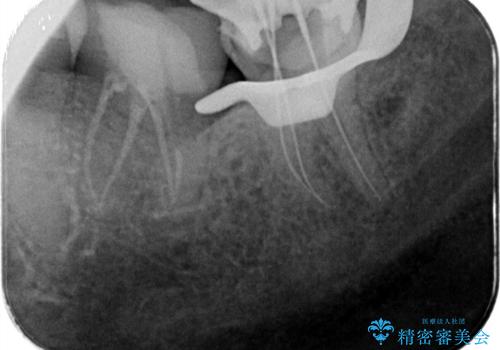

レントゲンや口腔内所見にて以下のような説明ののち、患者様が保存を希望されたため、当院では根管治療~オールセラミッククラウンにて修復処置を行いました。痛みも消えて、経過良好です。

病気の原因は細菌であるため、細菌数を減らすための処置として一般的に②根管治療という選択肢がある。再根管治療の場合は病気が治るのは7割ぐらいであり、それでも治らない場合は意図的再植術を行い9割近くまで成功率を高めることができる。ただし、今回のケースでは根尖が湾曲しているため意図的再植時の破折リスクが高いため適応は難しい。また、根尖の病変が治ったとしても、歯周病、カリエス、脱離や破折リスクがあり治療後抜歯になる可能性もある。治らない可能性や治療したとしても抜歯になる可能性があることを考慮し、③抜歯の選択肢をとる場合もある。